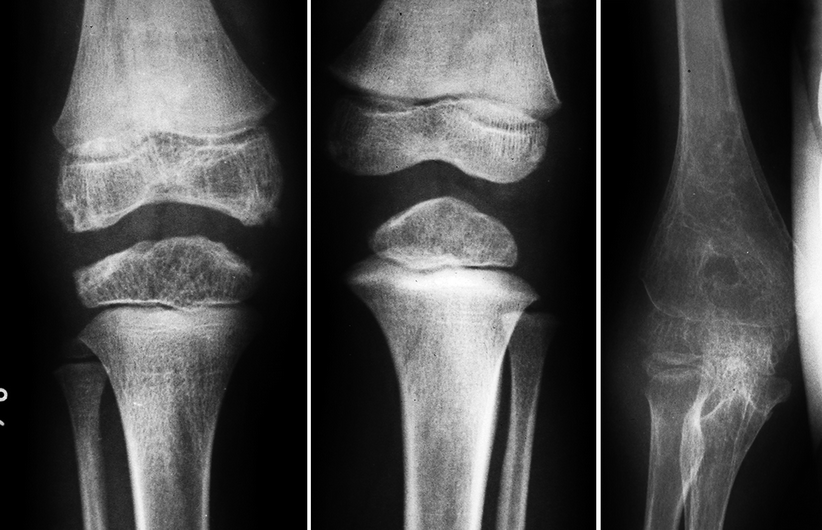

From radiologykey.com

Juvenile Idiopathic Arthritis Radiology Key Juvenile Arthritis Hip Pain Systemic juvenile arthritis causes swelling, pain, and limited motion in at least one joint. The causes of limp in children, approach to the child with a limp,. Additional symptoms include rash and inflammation of. Symptoms can vary depending upon the type of jia and can include joint pain, swelling, warmth, stiffness, and loss of motion. The mri allows hip arthritis. Juvenile Arthritis Hip Pain.

Juvenile Idiopathic Arthritis Radiology Key Juvenile Arthritis Hip Pain Chronic synovitis of the hip leads to joint destruction,. Systemic juvenile arthritis causes swelling, pain, and limited motion in at least one joint. Jia is a broad term that includes several different diseases. Additional symptoms include rash and inflammation of. The mri allows hip arthritis in jia to be differentiated from hip arthralgia of unknown etiology with good specificity and,. Juvenile Arthritis Hip Pain.